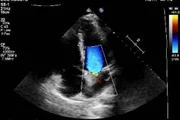

3 de 8 Vittor Fernando compartilha fotos da bala que atingiu seu coração Reprodução/Instagram @vittorfernando